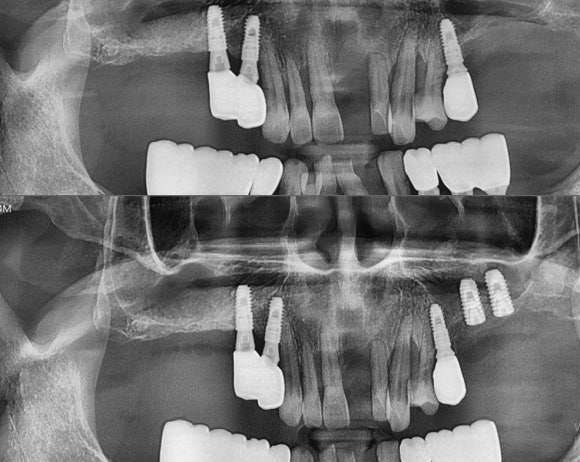

#26, 27 임플란트 식립 with 상악동 거상술 & 뼈이식

다른 치아를 봐도 잇몸뼈가 다 녹아 내려서 치아가 흔들림. 발치만이 치료가 되는 경우임.

뼈가 없어서 (나사를 박을 벽돌이 없어서),

상악동 거상술과 함께 뼈이식을 하고, 1-2mm 높이를 가진 잔존 잇몸뼈에 임플란트를 심고 묻어둔다.

상기 환자는 전신질환이 없고 젊은 50세 초반 건장한 남성이기 때문에 뼈이식과 임플란트 식립을 동시에 함.